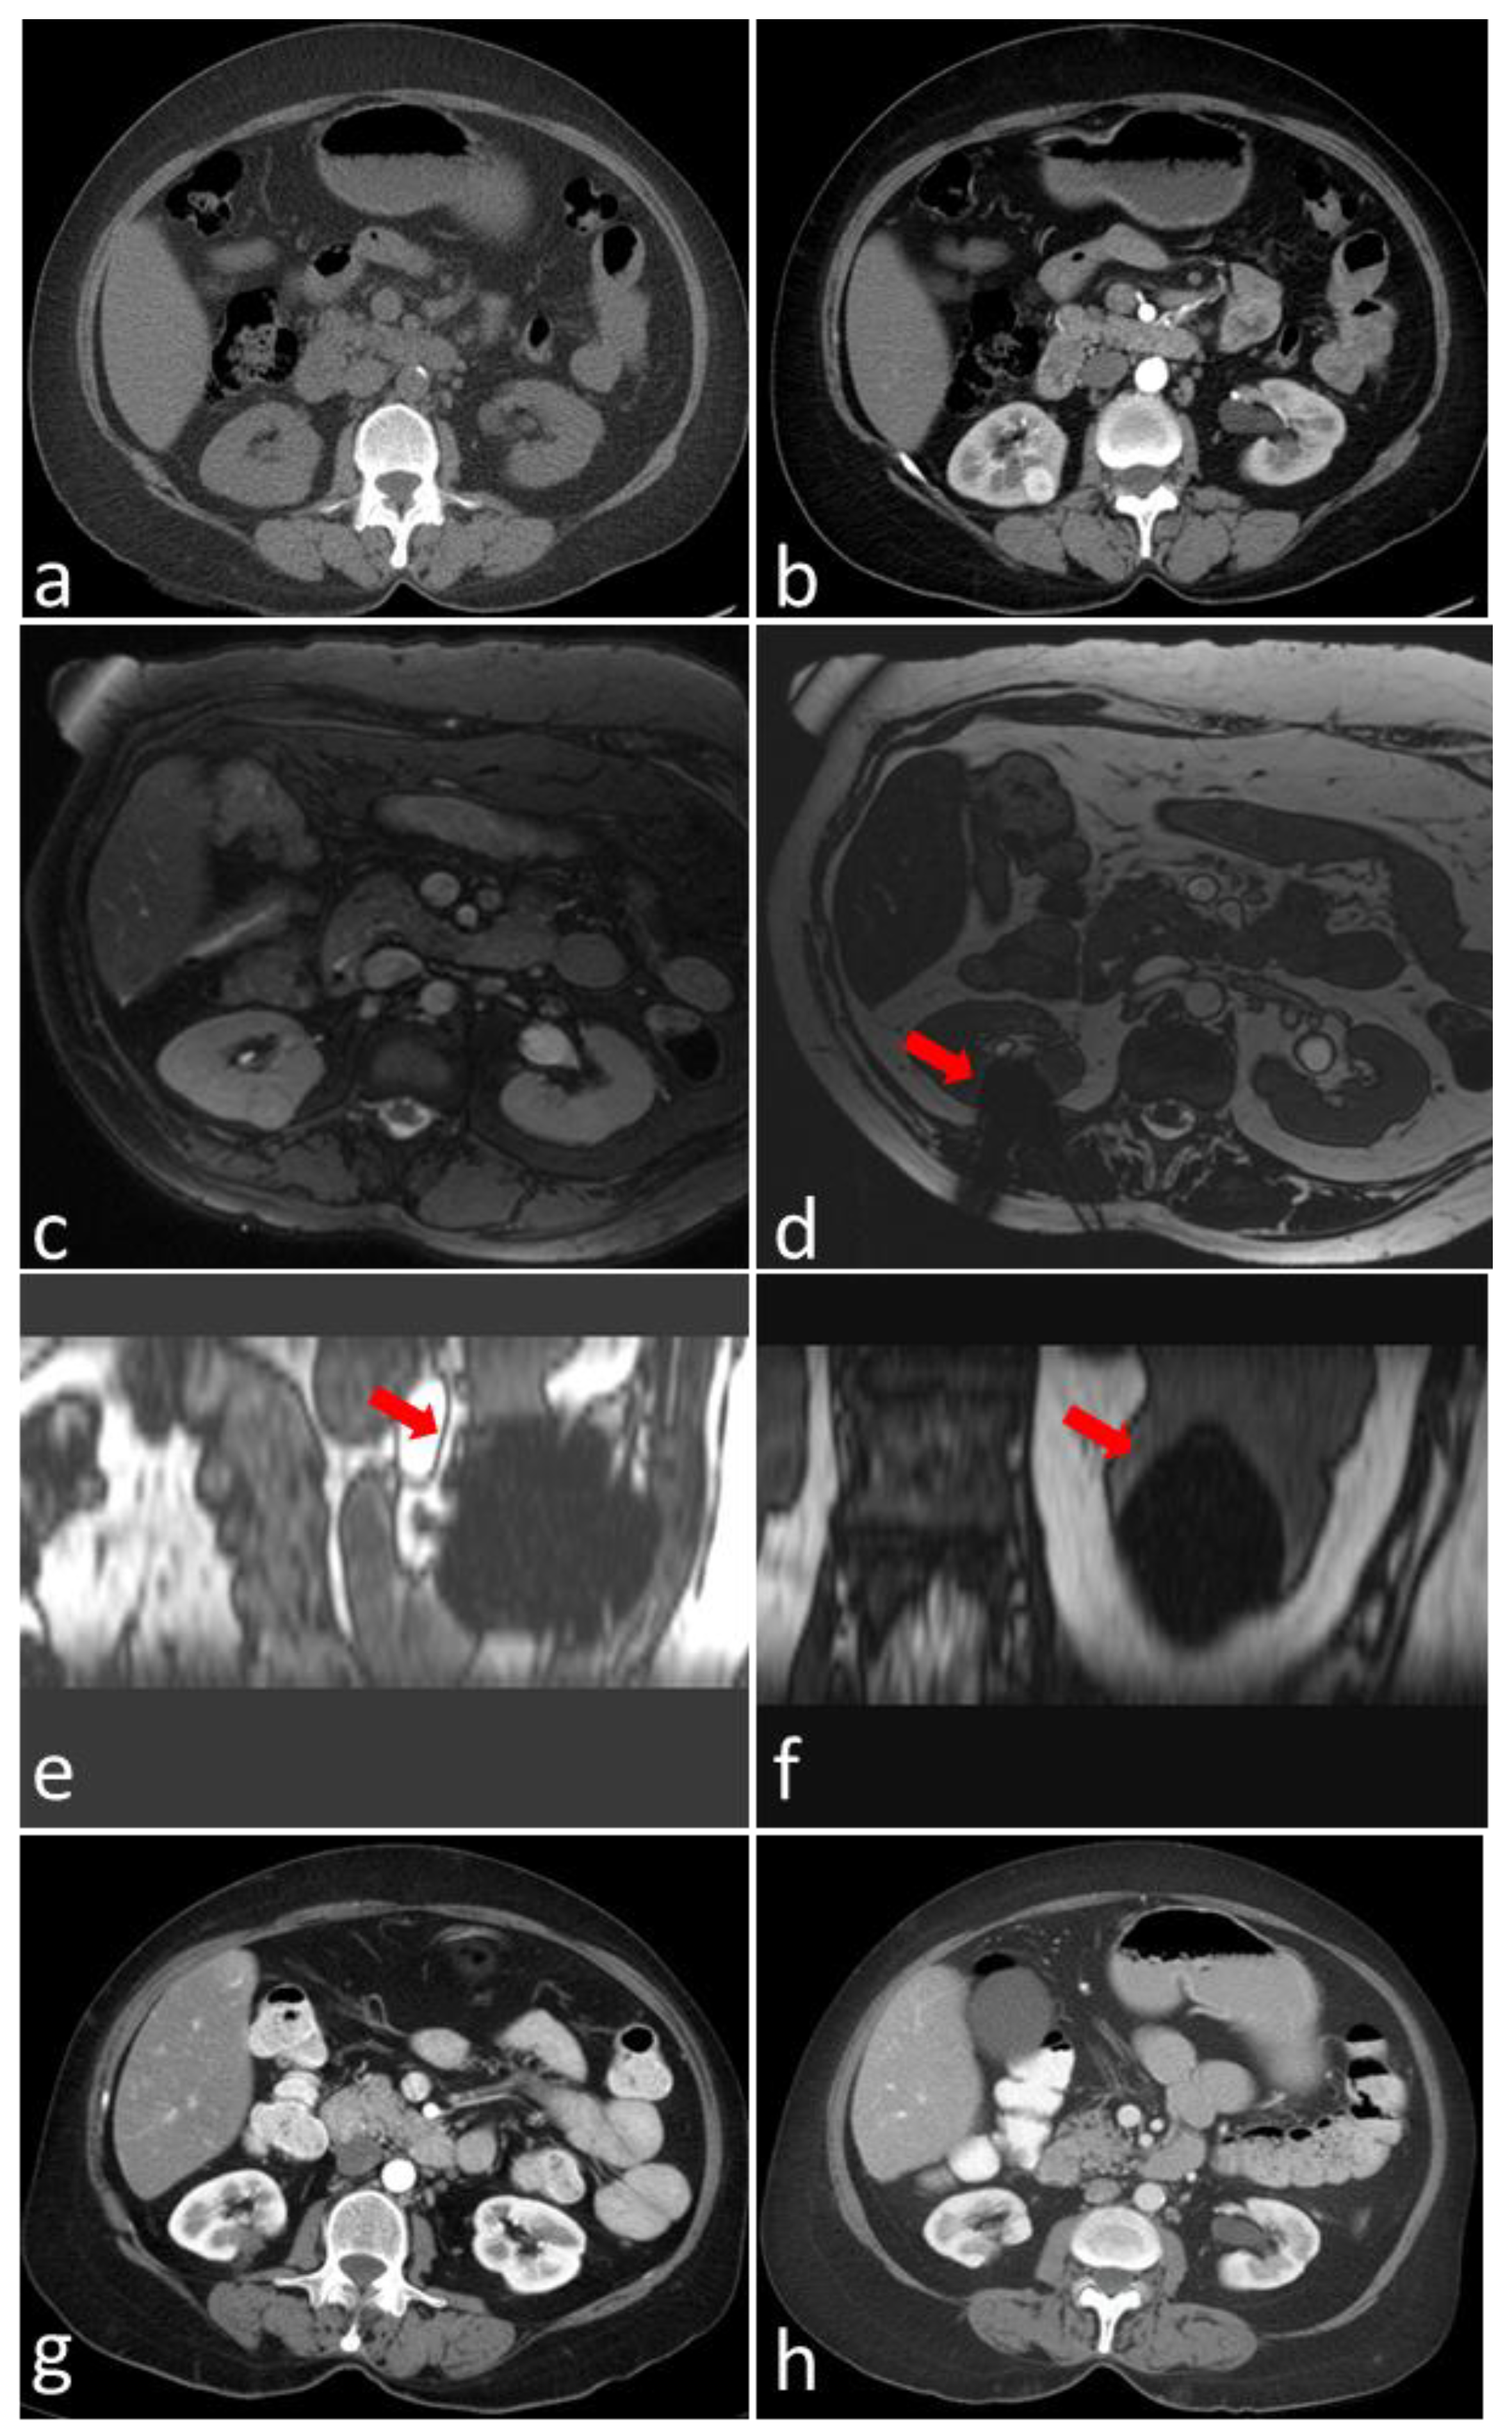

Magnetic-Resonance-Imaging-Guided Cryoablation for Solitary-Biopsy-Proven Renal Cell Carcinoma: A Tertiary Cancer Center Experience

- De Marini, P.; Cazzato, R.L.; Garnon, J.; Dalili, D.; Leonard-Lorant, I.; Leclerc, L.; Autrusseau, P.A.; Auloge, P.; Weiss, J.; Tricard, T.; et al. Safety and oncologic efficacy of percutaneous MRI-guided cryoablation of intraparenchymal renal cancers. Diagn. Interv. Imaging 2021, 102, 531–538. [Google Scholar] [CrossRef] [PubMed]

- Cazzato, R.L.; De Marini, P.; Leonard-Lorant, I.; Leclerc, L.; Auloge, P.; Tricard, T.; Dalili, D.; Garnon, J.; Lang, H.; Gangi, A. Safety and Oncologic Outcomes of Magnetic Resonance Imaging-Guided Cryoablation of Renal Cell Carcinoma: A 10-Year Single-Center Experience. Investig. Radiol. 2021, 56, 153–162. [Google Scholar] [CrossRef] [PubMed]